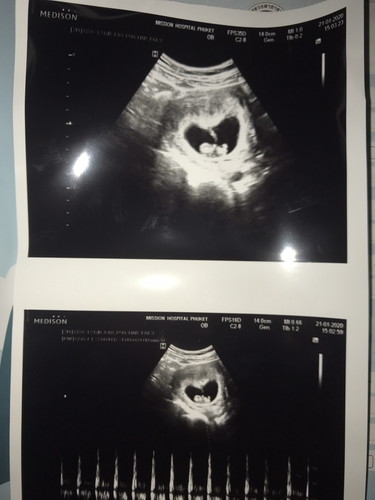

ซาวด์ 8W6D (คุณแม่ เป็นมะเร็งไทรอยด์ แต่รักษา จนหาย แล้ว )

วันนี้ไปฝากครรภ์ และซาวด์ เห็นน้องชัดมาก กำลังดิ้น ดุ๊กดิ๊กๆ เหมือนโบกมือ ทักทาย หมดให้ฟังเสียงหัวใจด้วย หมอบอกหัวใจแข็งแรง นอนอยู่คนเดียว แถมนอนอยู่ในที่ๆดีด้วย คุณแม่สามารถ ลุยงานหนักได้หมอไม่ห่วง กีใจมากๆ เพราะคุณแม่เป็นมะดร็ง ไทรอยด์ แต่ทำการผ่าตัดและทำรังสี เรียบร้อยหมดแล้ว ตอนแรกก็กังวล แต่พอวันนี้ ได้เห็นน้อง ตอนซาวด์ ทำไรไม่ถูกเลย น้ำตาคลอเบ้า ได้แต่ยืนอึ้ง เพราะเคยได้ยินมาว่าคนที่ถูกตัดค่อมไทรอยด์ จะมีโอกาศ มีลูกยาก หรือ ลูกจะไม่แข็งแรงเหมือนคนปกติ แต่มาวันนี้โล่ง และดีใจสุดๆ